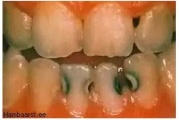

ANUG (äge nekrotiseeruv haavandiline gingiviit/parodontiit)